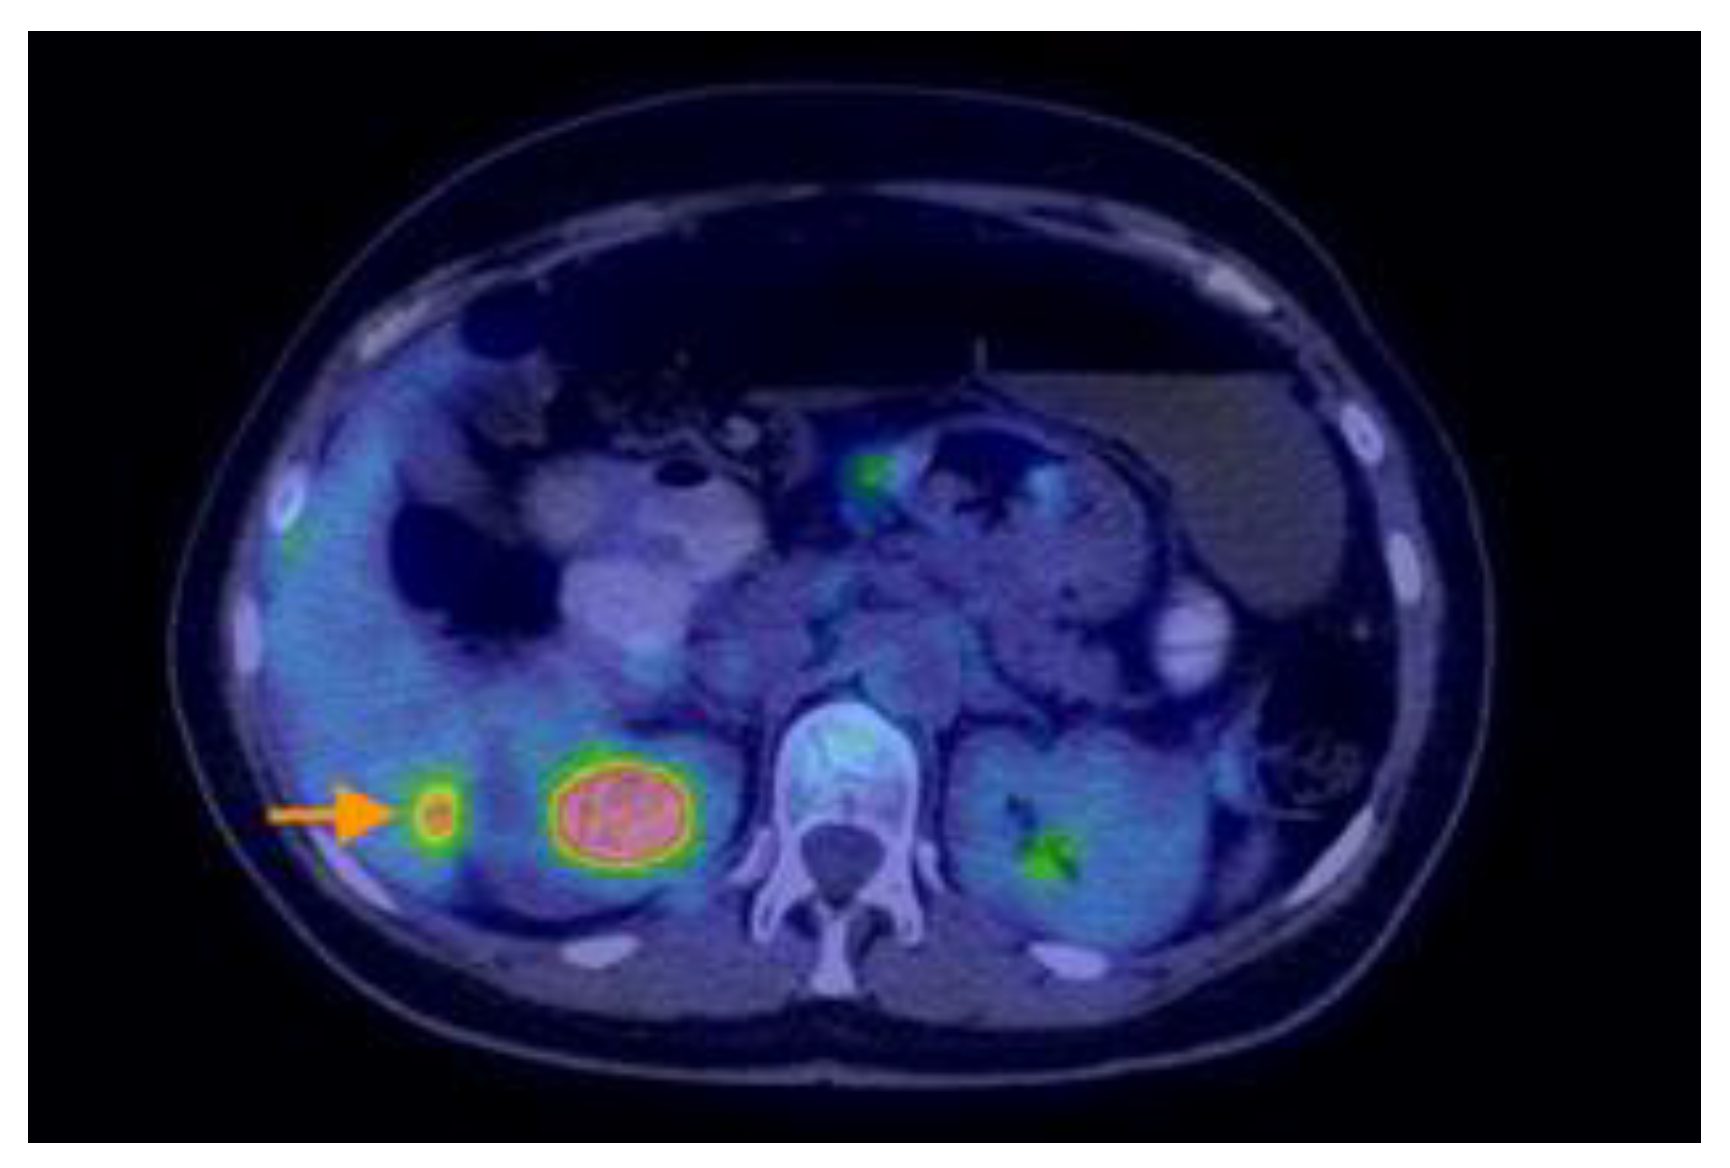

3.2.3. Imaging Findings, Diagnosis, and Differential Diagnosis